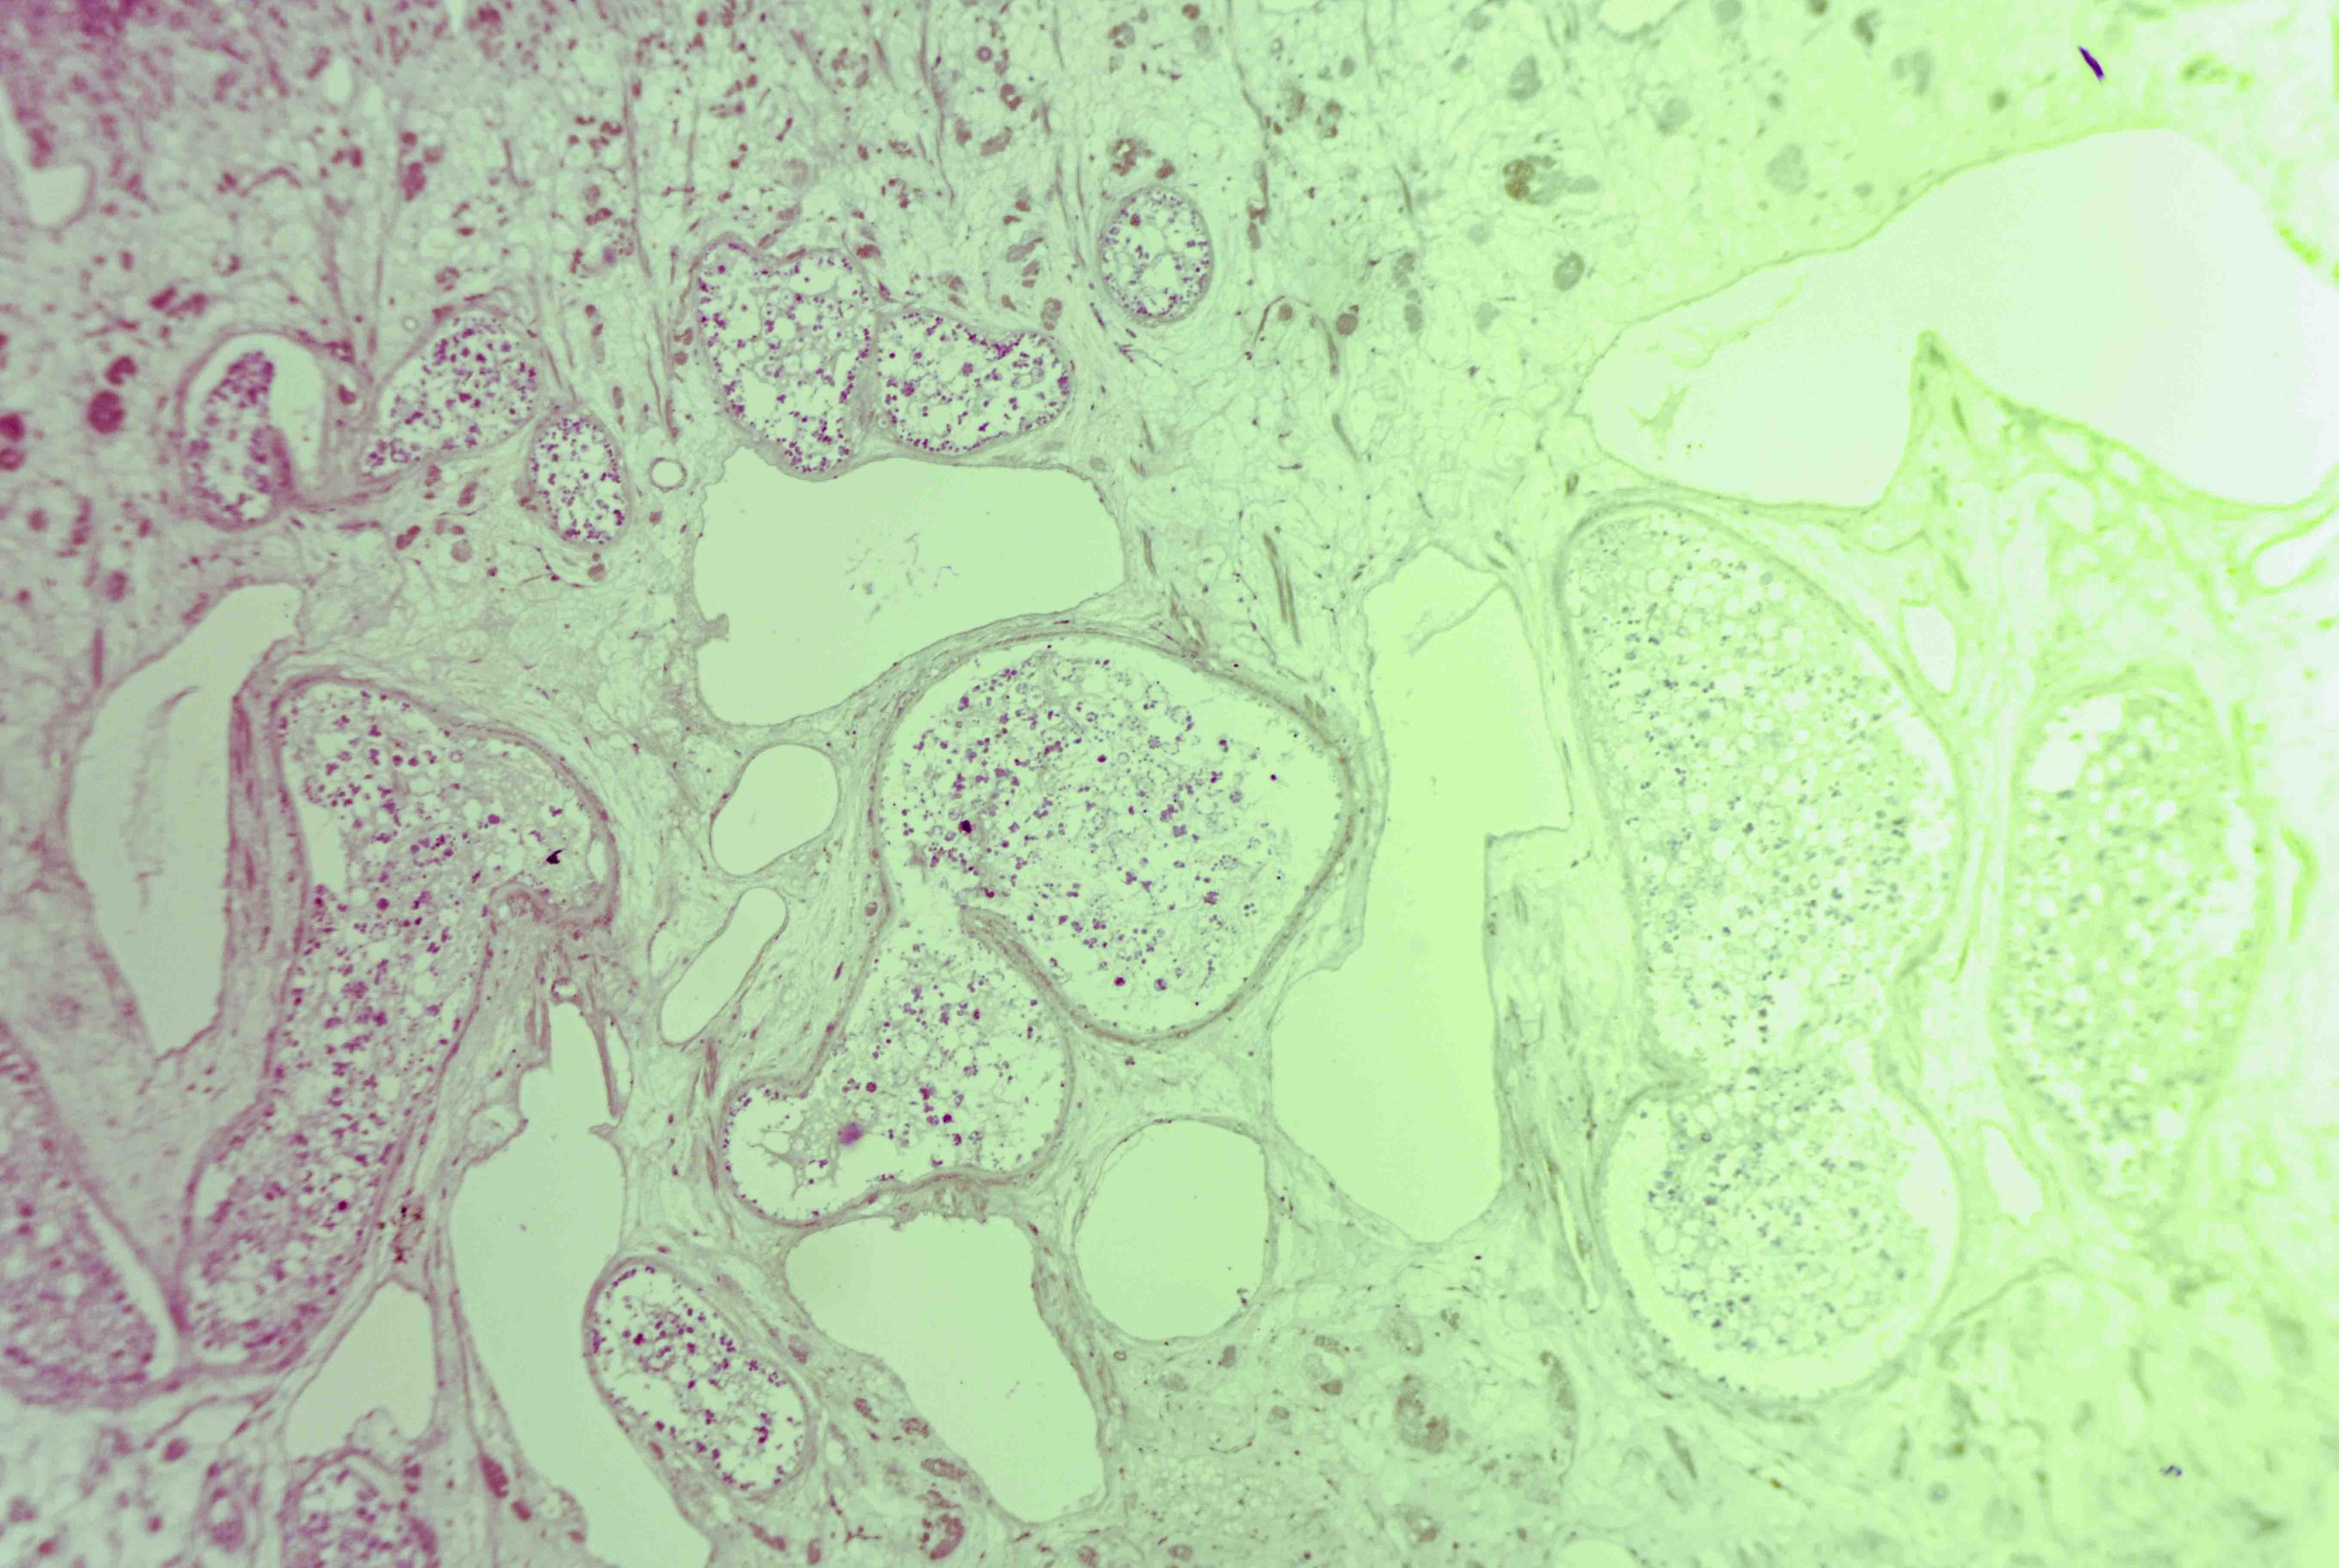

At first glance, a liver fluke is a simple, leaf‑shaped flatworm. Under magnification, however, a cross‑section reveals a labyrinth of chambers and cells, like stained‑glass windows filled with pink and purple mosaics. These sections show the parasite’s densely packed tissues, reproductive organs and digestive sacs nestled within its protective tegument.

This creature’s body is dorsoventrally flattened and oval, resembling a faint brown leaf. Adult flukes can reach about 3 centimetres in length and 1.5 centimetres in width, with a broader front tapering to a blunt posterior.

The surface of the fluke is wrapped in a syncytial tegument—a scleroprotein‑rich skin enveloped in glycocalyx—that protects the parasite from digestive enzymes and allows nutrient absorption.

Yet there is an eerie beauty in their design. The intricate patterns seen in histological sections hint at the fluke’s complex adaptations—suckers, tegument, branched gut and prolific reproductive tissues—all evolved to exploit its ecological niche.